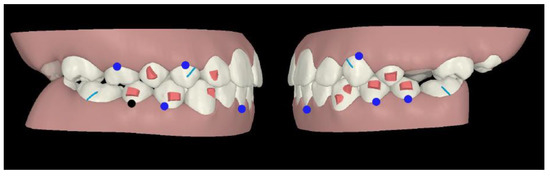

An Invisalign® “Teen” package was chosen, as it allowed to ask for a multi-phase treatment: in fact, it is possible to ask for additional aligners at any stage of tooth eruption. Compliance indicators were provided on the buccal area of the aligners in order to monitor patient’s adherence during treatment. The first phase of treatment was scheduled in late mixed dentition: horizontal attachments were placed over mandibular first and second bicuspids as posterior anchorage to allow intrusion forces of mandibular incisors area, whereas incisors did not require attachments (Figure 2).

Figure 2.

Treatment plan phase I.

On the maxillary right first bicuspid, the optimized rotation attachment was placed for its distal rotation and lingual inclination (Figure 2).

On the maxillary right lateral incisor, an optimized attachment on the labial surface and a pressure point on lingual surface were placed to achieve intrusion and mesial rotation (Figure 2).

On the mandibular left canine, an optimized attachment was planned for root control during its mesial rotation and distal translation, whereas on the mandibular right canine the optimized attachment was placed for its mesial rotation. Moreover, their intrusion was planned (Figure 2).

In first and second phase, precision cuts were designed on the aligner surface for Class II elastics in order to obtain a mandibular advancement (Figure 2 and Figure 3).